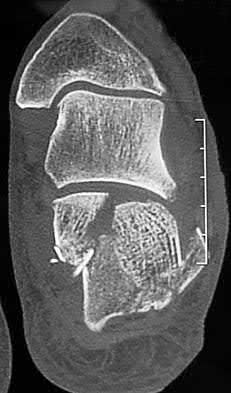

A 25-year-old female is involved in a motor vehicle collision. She presents with the isolated injury seen in Figures A through D. Her leg is swollen but her skin is intact. She has no clinical signs of compartment syndrome. Which of the following treatment options will allow for maintenance of fracture alignment and minimize the risk of soft tissue complications?

The patient presents with a closed distal third metaphyseal-diaphyseal distal tibia fracture with simple intra-articular extension. Immediate intramedullary nailing along with percutaneous fixation of the articular component provides appropriate restoration of length, rotation and alignment and minimizes the risk of wound complication.

Displaced distal third tibia fractures may be associated with simple intraarticular extension. Operative treatment of intra-articular distal tibia fractures has historically been performed with open reduction and internal fixation. Early open reduction and plate fixation of pilon fractures has been associated with high rates of infection and wound complication. In select patterns with simple articular extension, percutaneous screw fixation and medullary nailing may provide appropriate reduction with minimal soft-tissue risk.

Figures A and B demonstrate a distal third tibial shaft fracture with simple intra-articular extension. The axial and coronal CT cuts in Figures C and D further clarify the articular injury. Illustrations A and B demonstrate a comminuted distal third tibial fracture with simple intra-articular extension. Illustrations C and D are fluoroscopic images of the same injury after intramedullary nailing and percutaneous fixation of the articular component.